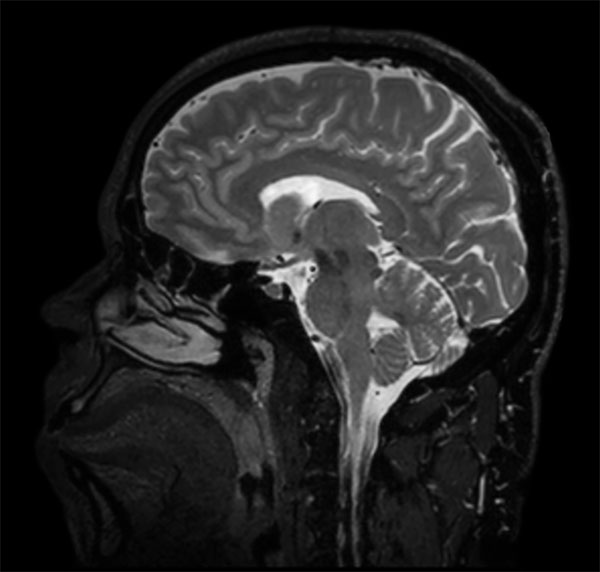

dS SENSE in Brain Imaging

Used Solution

• Clinical Application